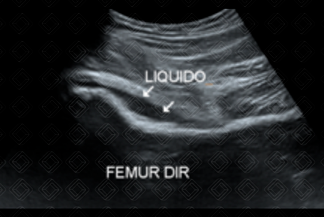

Descrição das figuras 1 e 2: Ultrassonografia de quadris. Menino, paciente de 9 anos de idade, com claudicação à direita. Observa-se que no quadril direito há abaulamento da cápsula articular anteriormente, que contém líquido (setas brancas). Já o quadril esquerdo está completamente normal, sem abaulamento da cápsula iliofemoral.

• Ultrassonografia do quadril ( exame de escolha ): Solicitada para avaliação e procura do derrame articular. Durante o exame, observa-se a elevação da cápsula iliofemoral ao nível do colo femoral (como na imagem acima). Importante lembrar que, como a sinovite é uma condição comum na população pediátrica, a ultrassonografia acaba sendo o método mais viável por ser uma exame de mais rápida realização e sem necessidade de sedação;